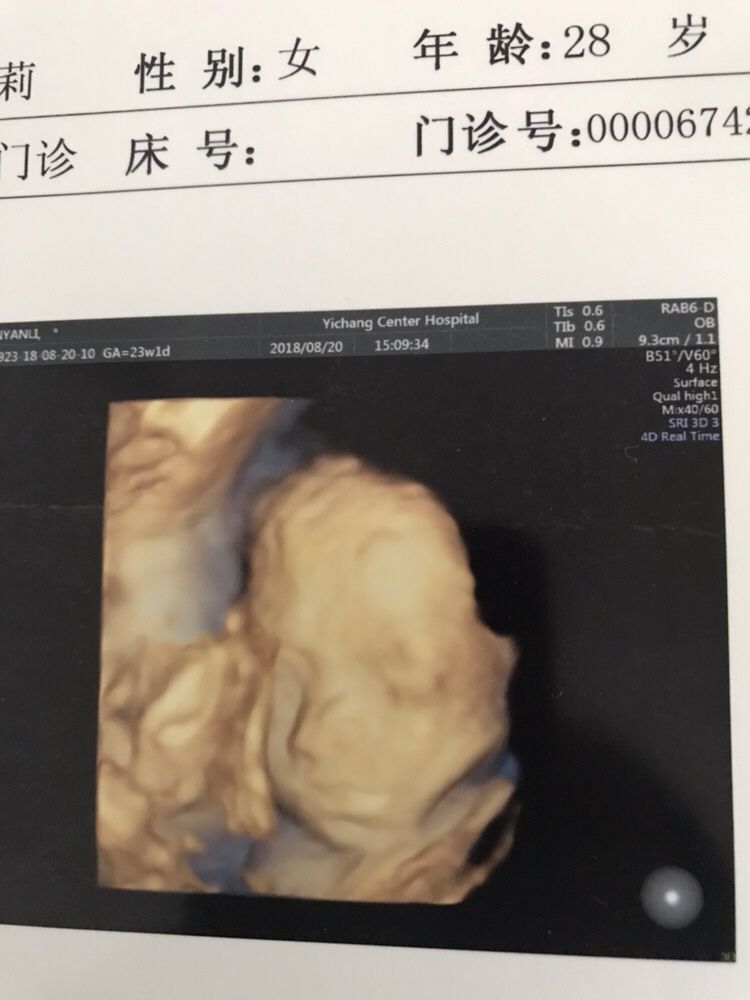

孕28周+5天